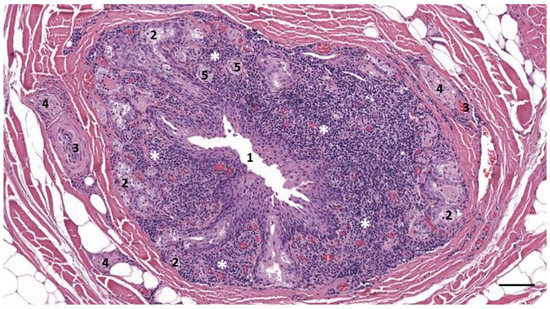

3.1. Ear Canal-Associated Lymphoid Tissue (ECALT)

3.2. Nodular Lymphoid Tissue

3.3. Immunoreactive Tissue